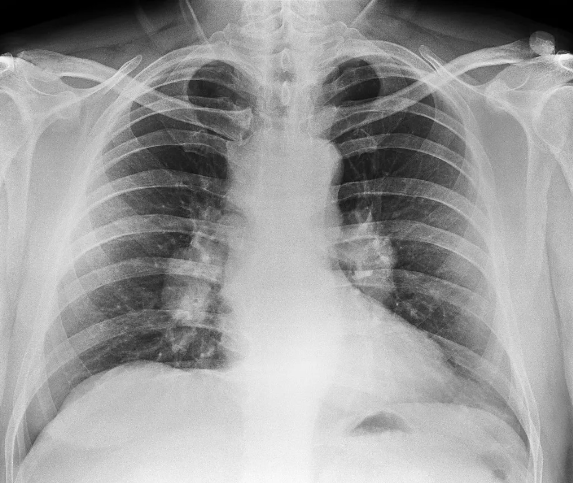

为何近两年查出肺结节的人这么多? 2024-05-30

目前,我国有1.5亿肺结节高危人群群体,每年新发现或者新诊出肺结节患者达到1000万~2000万,肺结节的早期筛查也是临床上最常见的问题。这两年,不少人在做CT时也发现,自己和周围人在检查中发现肺结节的比例也增加了...